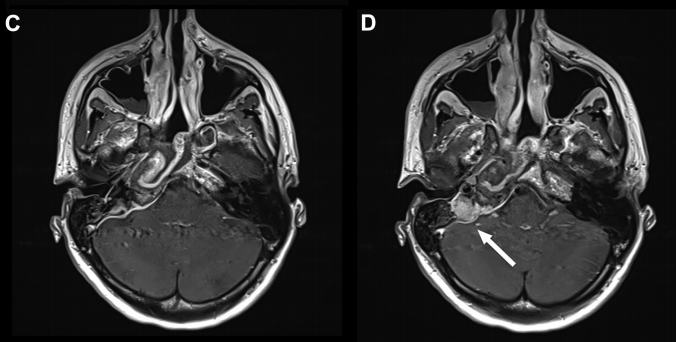

▼术后(C、D)图像显示病灶次全切除,并显示鼻中隔瓣修复良好。显示岩尖然后面的小部分残留病灶(C、D、箭头)。值得注意的是,除了鼻中隔后三分之二和蝶窦外,全部其他鼻内正常组织结构均被保留完整无损。